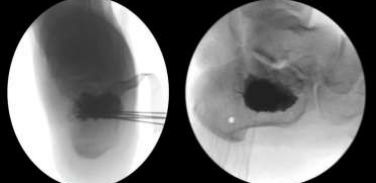

To further stabilize the fracture and maintain the restored articular congruity, the minimally invasive procedure incorporated the use of Vertebral Body Stenting System (VBS) from DePuy Synthes. Then 4 K-wires was introduced from lateral to medial at the inferior part of the created gap to prevent inferior displacement of the stent. Through the previously created lateral stab incision, a medium-sized Vertebral Body Stent with Balloon was introduced into the fracture void. This pre-inflated stent, with a maximum volume of 4.5 ml and maximum inflation pressure of 30 ATM, served as a crucial tool for both reduction and internal support. Inflation proceeded under fluoroscopic guidance, gradually increasing pressure until an appropriate resistance was encountered at around 20 ATM (Figure 7). The inflated stent acted as a highly effective reduction tool. Its expandable nature compacted the softer inner bone within the calcaneus, simultaneously creating a void space and elevating the depressed posterior facet fragment back to its anatomical position (Figures 9, 10, 11, and 12). This restoration of height and improved articular surface alignment contributed significantly to fracture stabilization were the inferiorly placed K-wires prevented downforce. Following successful VBS deployment, and stent visualization to be holding the reduction radiopaque, injectable polymethyl methacrylate cement (VERTECEM V+ CEMENT KIT) from DePuy Synthes was utilized as a void-filling agent. Under fluoroscopic control, 4 ml of cement (2 syringes) were injected into the newly created cavity within the calcaneus (Figure 8). This cemented augmentation provided additional stability and maintained the fracture reduction. After a ten-minute cement curing period, the temporary Kirschner wires were safely removed. The surgical site was meticulously closed, dressed, and supported with a below-knee backslab for additional immobilization. Final intraoperative radiographs confirmed satisfactory reduction, restoration of the crucial angle of Gissane, and appropriate cement distribution (Figures 13 and 14).